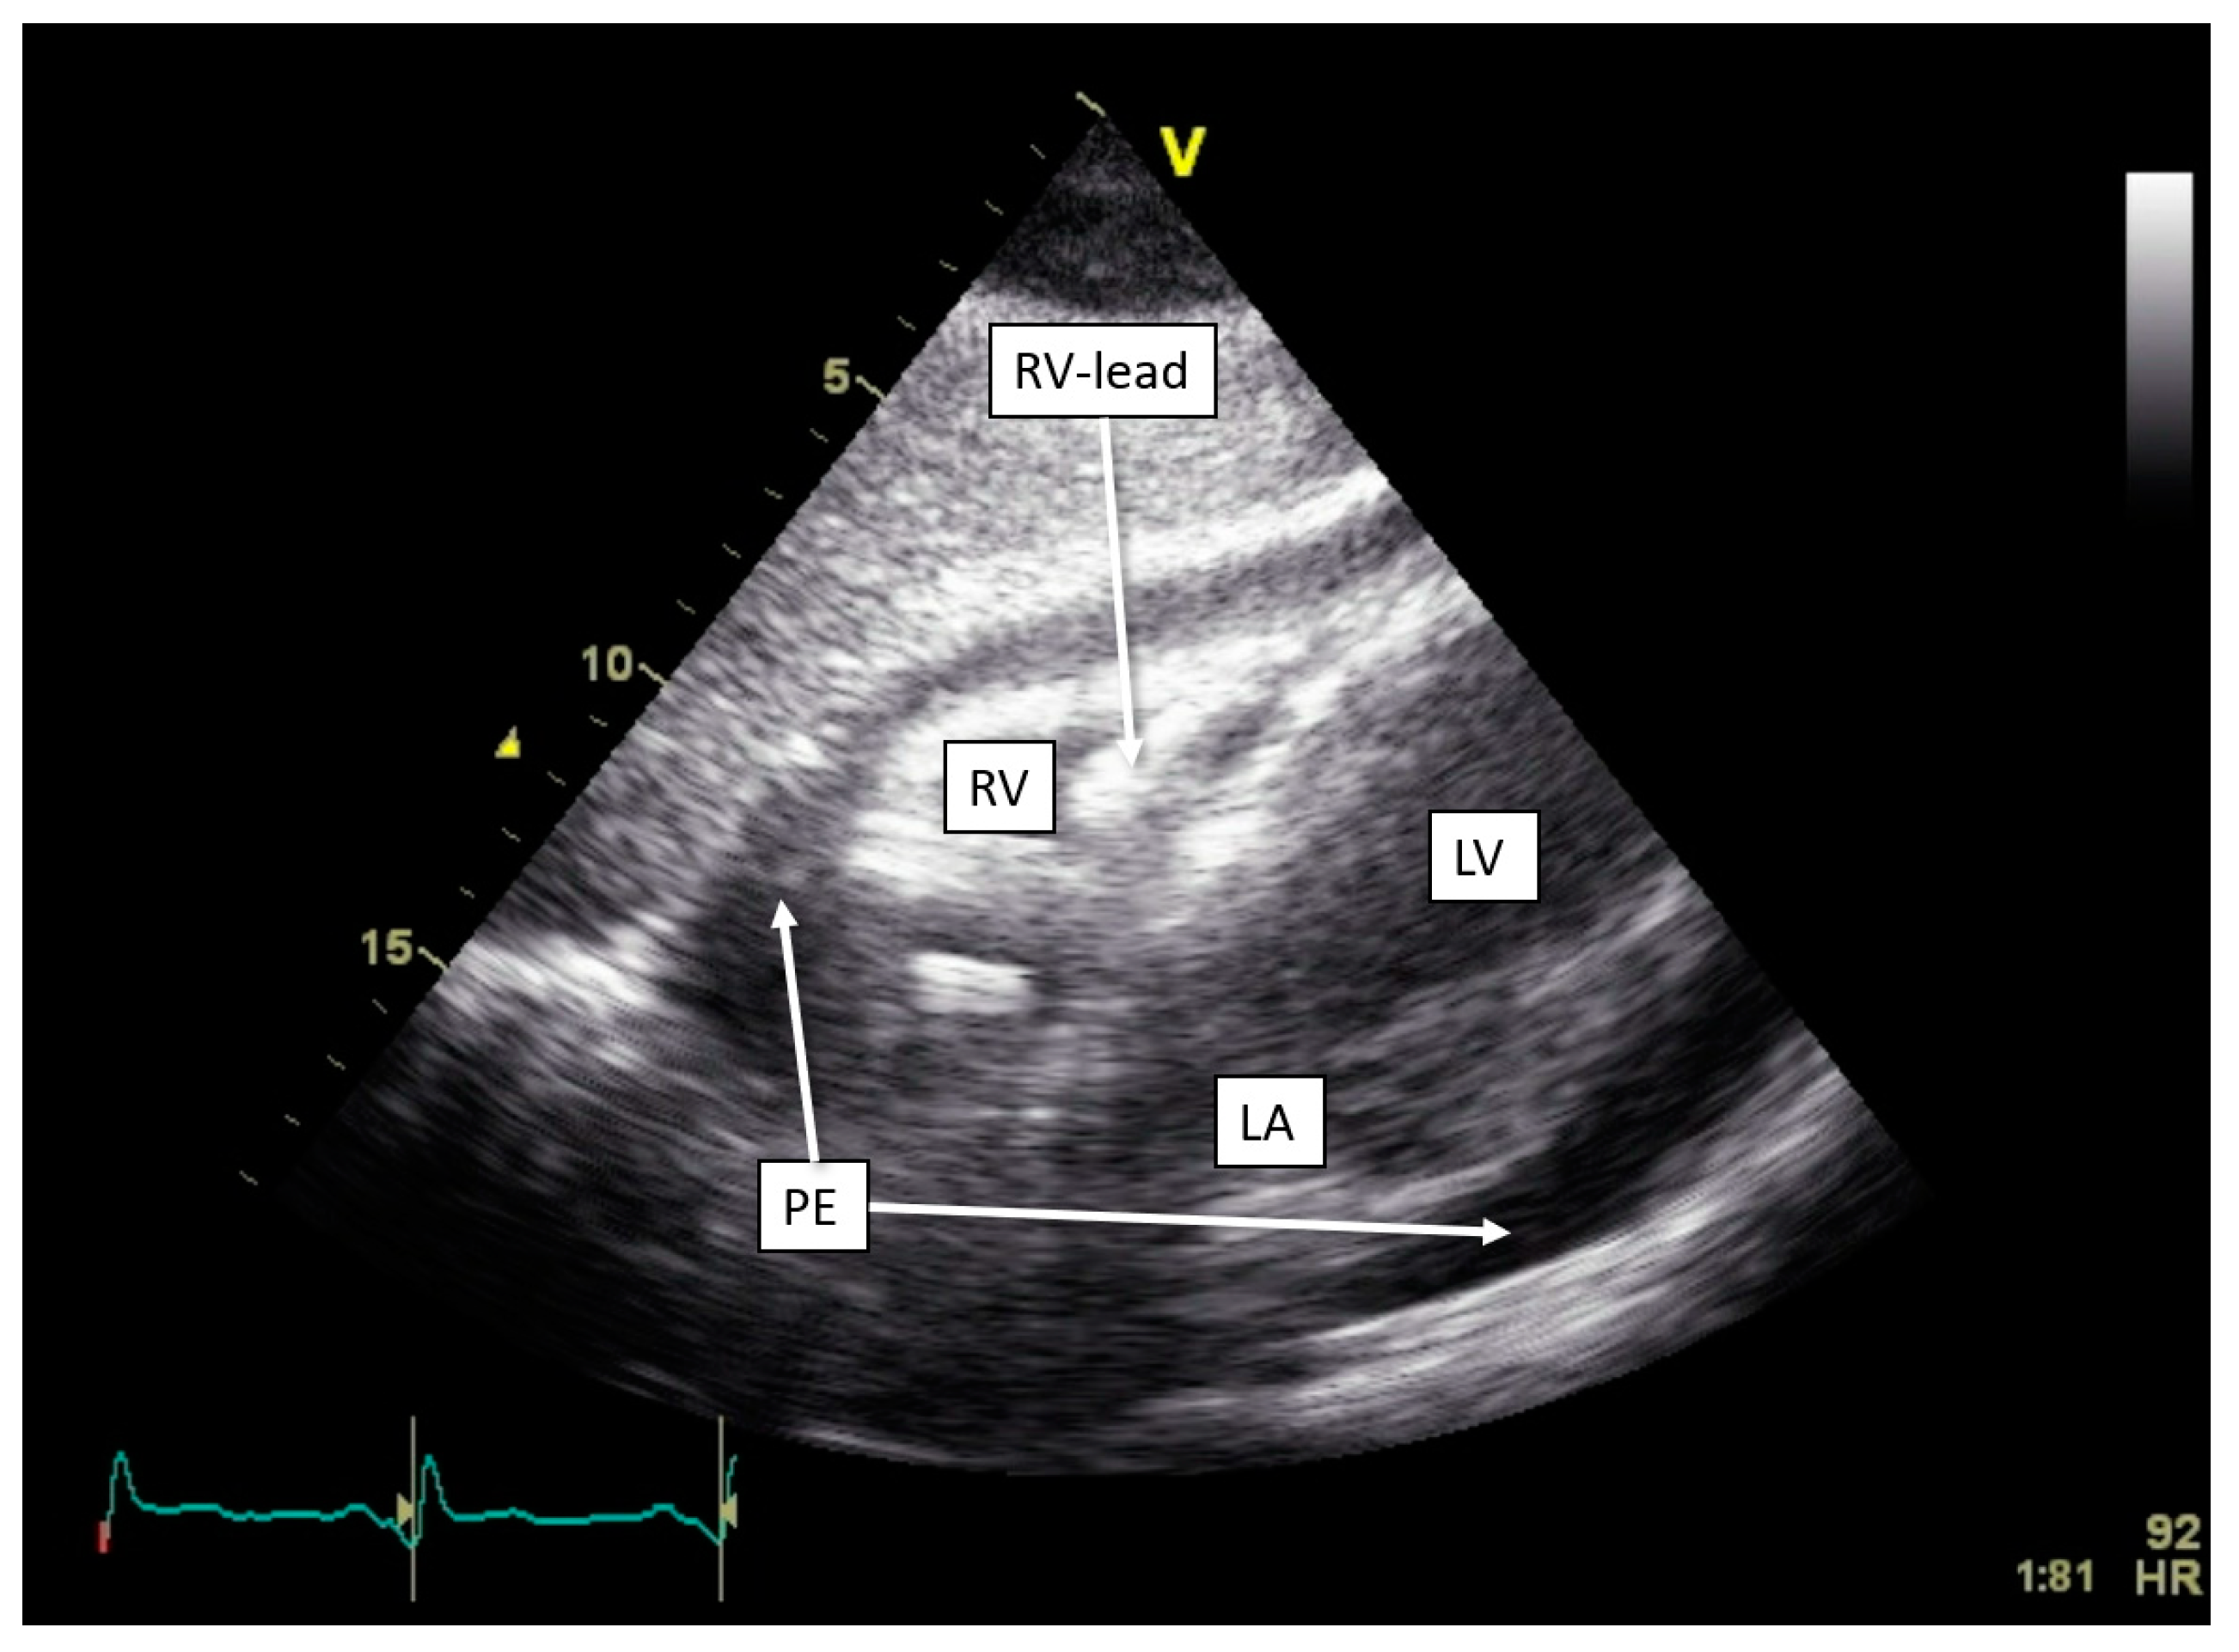

| Thoracic impedance alert | Pulmonary edema [22], pneumonia [23], and pericardial effusion (this review). | |